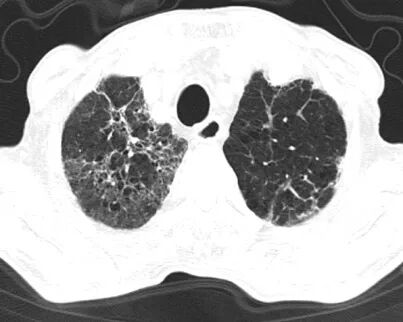

然而,病情的凶险程度远超预期,检查结果提示D-二聚体显著升高,CTPA提示右下肺动脉肺栓塞,肺部感染亦较前明显进展,病情进一步恶化。在呼吸与危重症医学科主任李芳芳带领下,团队迅速调整方案,加强抗凝与抗炎治疗。

胸部CT及CTPA